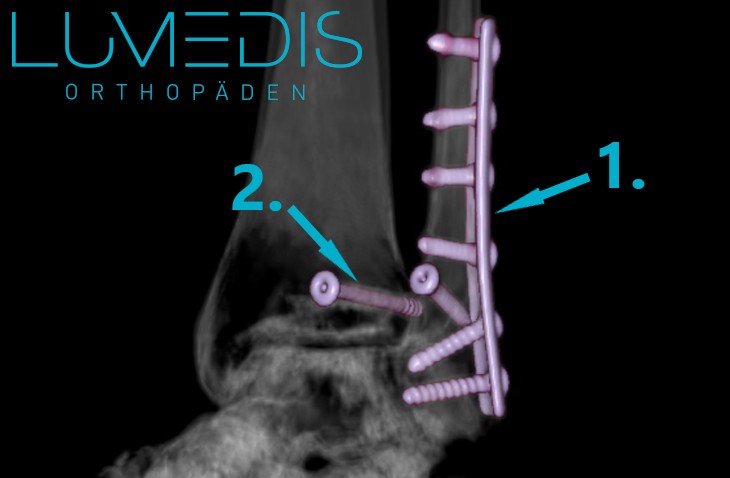

Röntgenbild eines Sprunggelenksbruchs mit Metallplatte und Schrauben

Die Therapie einer Weber B Fraktur ist in der Regel operativ. In Vollnarkose wird die Stelle des Bruchs eröffnet, die Bruchränder gerichtet und diese meistens durch Schrauben oder Platten fixiert, bevor die Haut wieder verschlossen wird.

Eine operative Behandlung einer Weber B Fraktur ist immer dann notwendig, wenn es sich um eine verschobene Fraktur handelt und wenn die stabilisierende Syndesmosen verschoben ist.

In diesem Fall könnte eine konservative Behandlung keine spätere Stabilität der Fraktur garantieren.